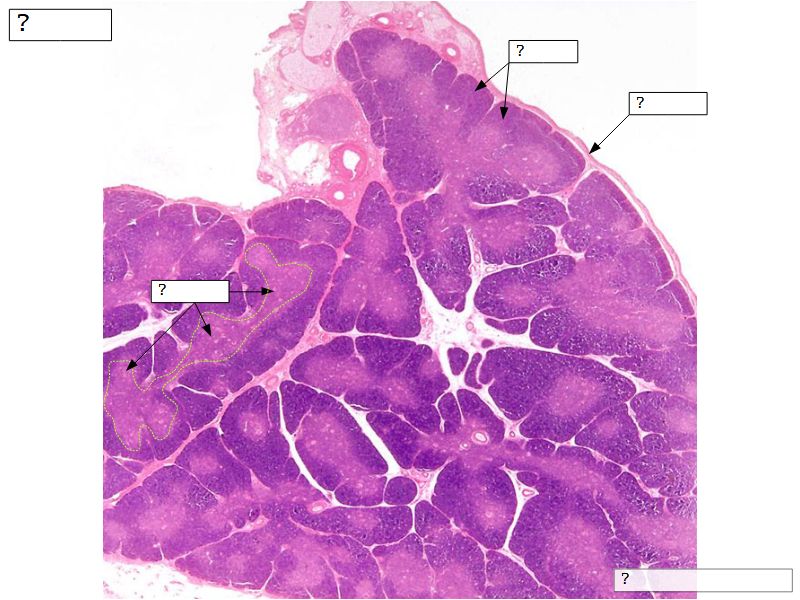

Fill in all the missing labels, and assess as you move through the slides. Answers on the down slide. It is important to do this using pen and paper, and not just glance through the images.